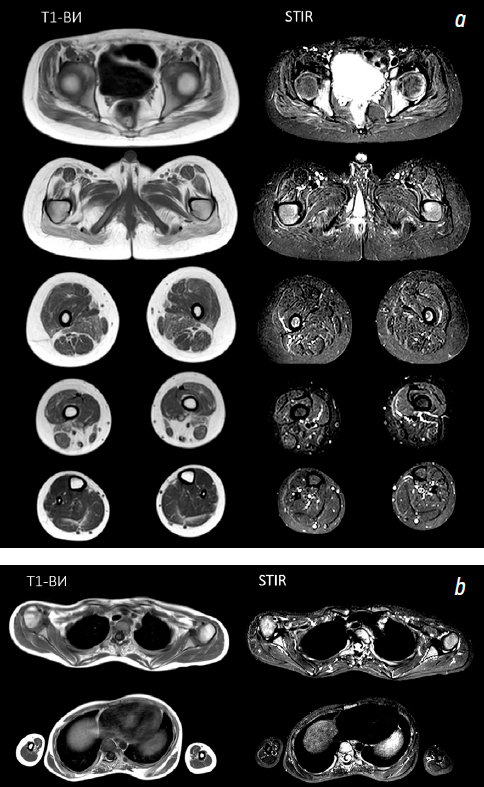

- Суслов В.М., Поздняков А.В., Иванов Д.О., и др. Количественная магнитно-резонансная томография как маркер эффективности терапии глюкокортикостероидами у пациентов с мышечной дистрофией Дюшенна // Педиатр. 2019. Т. 10, № 4. С. 31–37. doi: 10.17816/PED10431-37 EDN: XVWVYI